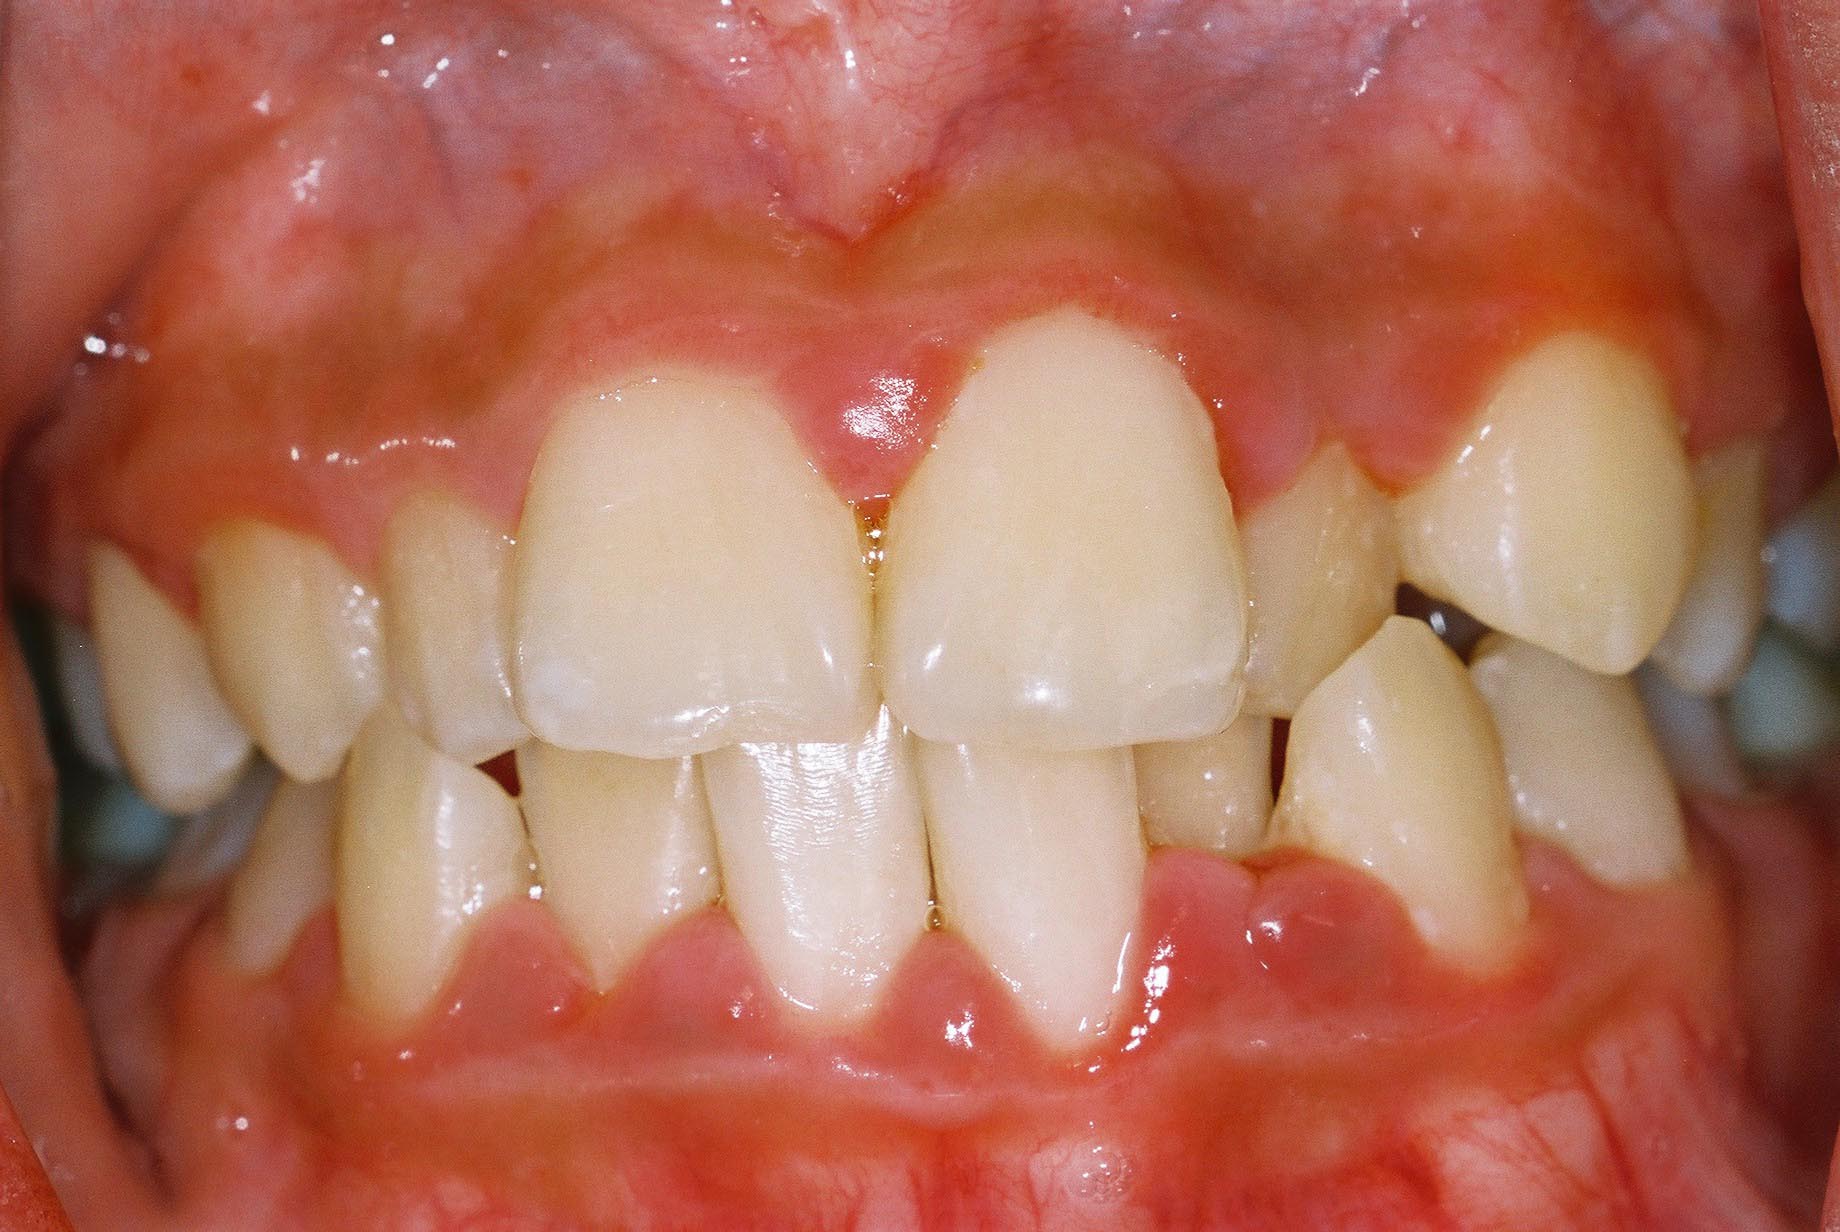

There are two major stages of periodontal disease: gingivitis and periodontitis. The earlier stage, gingivitis, is a mild form of gum disease caused by plaque build-up around the gum line which causes inflammation of the gums. If you neglect to brush or floss your teeth daily, this plaque build-up will trap bacteria and cause gum disease. Your gums will appear red and swollen, and you could experience bleeding when you brush or floss. If properly treated, it may be reversed.

•    Red, swollen or tender gums

•    Bleeding gums when you brush your teeth